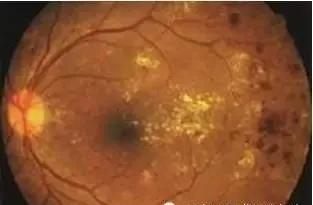

①糖尿病视网膜病变:有无视力下降以及下降的程度和时间;是否检查过眼底或眼底荧光造影;是否接受过视网膜光凝治疗 。